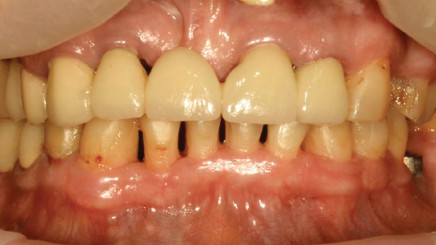

Пародонтит тяжелой степени

Результат через 2 недели

Параметры изменяются в зависимости от процедуры